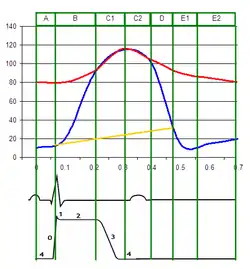

Pressures

Red = aortic pressure

Blue = left ventricular pressure

Yellow = left atrial pressure.

Ventricular pressure is a measure of blood pressure within the ventricles of the heart.[13]

Left

During most of the cardiac cycle, ventricular pressure is less than the pressure in the aorta, but during systole, the ventricular pressure rapidly increases, and the two pressures become equal to each other (represented by the junction of the blue and red lines on the diagram on this page), the aortic valve opens, and blood is pumped to the body.

An elevated pressure difference between the aortic pressure and the left ventricular pressure may be indicative of aortic stenosis.[16]